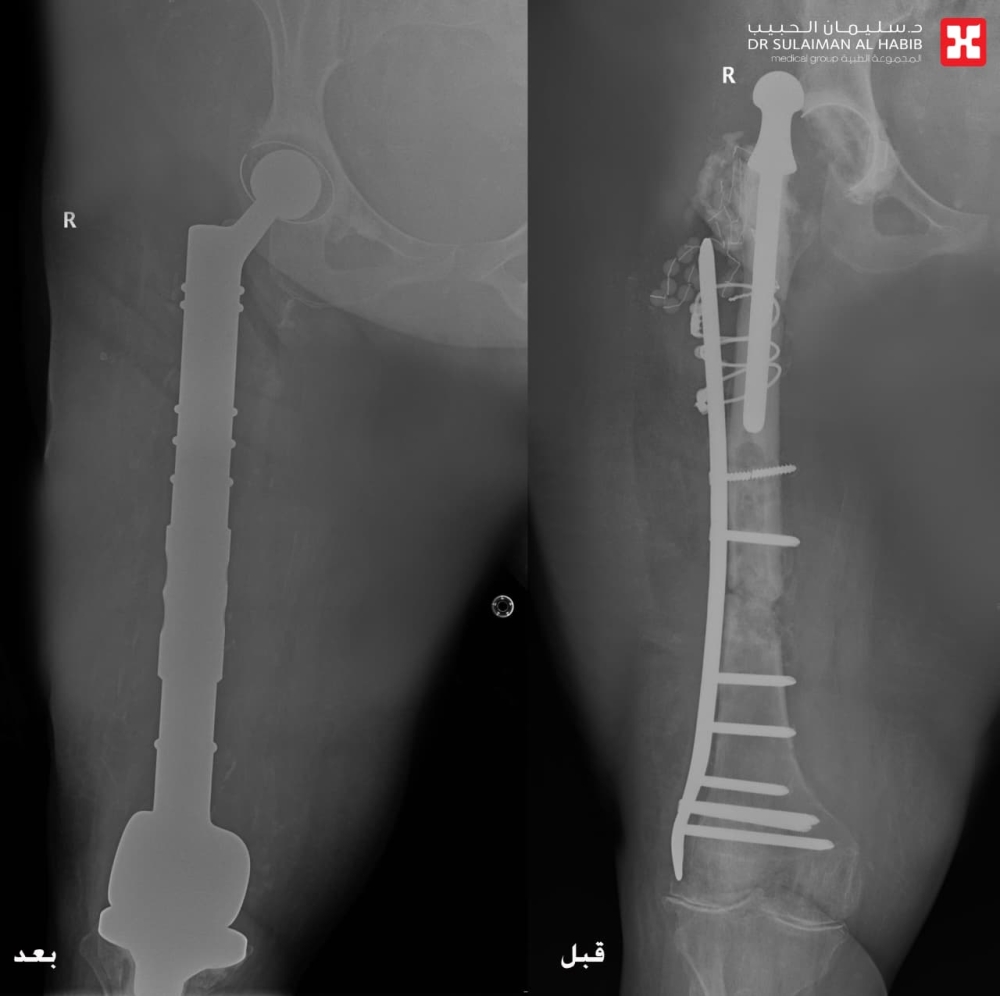

تمكن مستشفى الدكتور سليمان الحبيب بالخبر، من إعادة القدرة على الحركة والمشي لسيدة ستينية، ظلت طريحة الفراش منذ أكثر من “14” عاماً، بسبب مضاعفات عملية استبدال مفصل الورك الأيمن كانت قد خضعت لها قبل “30” عاماً، وأجرى لها فريق طبي قاده د. عبدالرحمن الرفاعي استشاري جراحة العظام وعظام الأطفال والتشوهات ومفصل الورك المتقدمة، جراحة معقدة وناجحة أنهت معاناتها.

وقال د. الرفاعي الحاصل على الزمالة السويسرية، أن المراجعة جاءت إلى المستشفى بحالة صحية معقدة، إذ أظهرت الفحوصات الدقيقة وجود التهابات حادة ومزمنة وورم التهابي منتشر في مفصل الورك أدى لخروجه، وكذلك في عظمة الفخذ ومفصل الركبة، كما أنها كانت مصابة بمضاعفات عدم الحركة “تقرحات الفراش” وتصلب المفاصل والظهر، إضافة إلى سوء الحالة الصحية العامة.

وتابع د. الرفاعي قائلاً أن الفريق الطبي وضع خطة علاجية متكاملة مكونة من عدة مراحل، بدأت بإزالة المفصل القديم والورم الالتهابي الذي بلغ وزنه “20” كجم، ووضع أجهزة داخلية تحتوي على مضادات لعلاج الالتهابات، وبعد التخلص منها، جرى استبدال كلي لمفصلي الورك والركبة، وعظمة الفخذ، في تدخل جراحي معقد استمر لـ”5″ ساعات، وتكللت جهود الفريق الطبي ولله الحمد بالنجاح التام، حيث نقلت المراجعة بحالة صحية مستقرة إلى غرفة التنويم، وتحسنت حالتها باضطراد مع العناية الطبية الحثيثة، وغادرت المستشفى بعد عدة أيام بحالة صحية ممتازة، ولاحقاً تخلصت من كافة الأعراض التي عانت منها طوال سنوات ما قبل العملية، حيث جاءت إلى المستشفى بعد عدة أسابيع مشياً على قدميها.